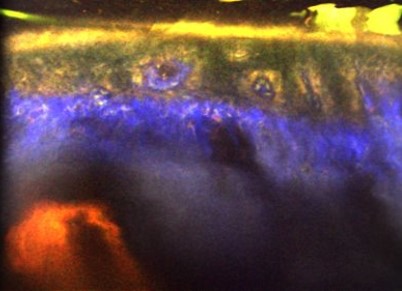

Click to view moreLeading imaging technologies advancing non-invasive dermatological diagnostics